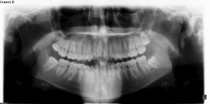

Wisdom teeth are the last teeth to erupt in the mouth, which is why they get the name "wisdom", we are older when they come in.  Unfortunately for many of us there just is not enough room for them to erupt normally.  In those cases the wisdom teeth are impacted, which means they are partially or totally under the gum or in the jaw and can't come in.

Impacted wisdom teeth can cause pain or infections, common reasons they are extracted.  They also are difficult to keep clean and are more prone to tooth decay.  Partially impacted teeth can not be filled.

We recommend removing impacted wisdom teeth, even when there are no complaints, before 30 - 35 years of age.